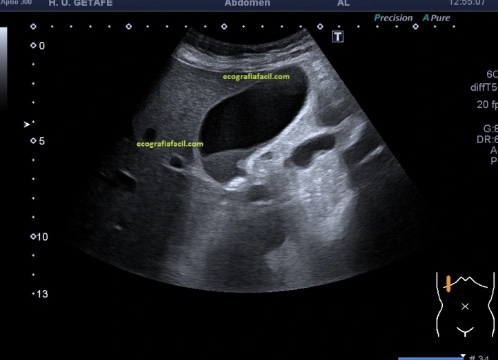

GLUTATION y BARRO BILIAR

Screenshot